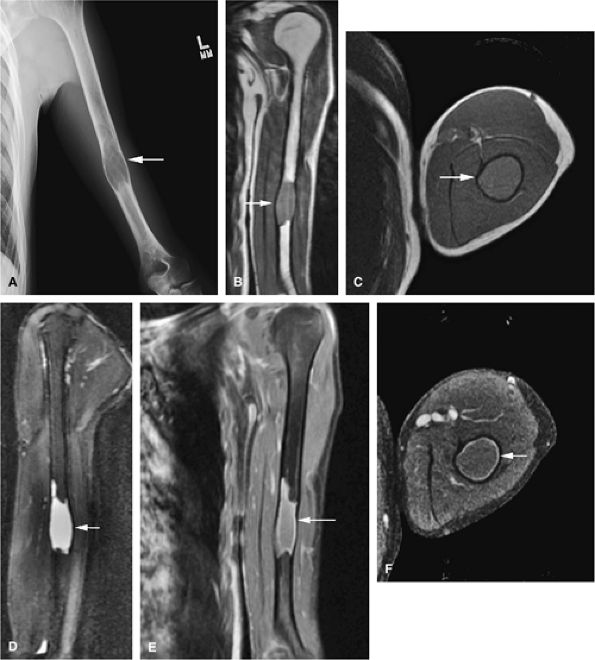

FIGURE 14-41 ● Monostotic fibrous dysplasia of the humerus. Anteroposterior radiograph (A) demonstrates an expansile lesion involving the humeral diaphysis (arrow). Fibrous tissue expansion of the medullary cavity is intermediate in signal intensity (arrows) on coronal T1-weighted image (B). Fibrous tissue expansion of the medullary cavity is intermediate in signal intensity on axial (C) T1-weighted image (arrow) and high in signal intensity (arrow) on a sagittal fat-suppressed T2-weighted fast spin-echo image (D). Fat-suppressed coronal (E) and axial (F) T1-weighted images following the intravenous administration of gadolinium demonstrate peripheral enhancement (arrows).

FIGURE 14-42 ● Monostotic fibrous dysplasia of the left femoral neck, a common location, demonstrates low signal intensity on a coronal T1-weighted image (A) and increased signal intensity on a fat-suppressed T2-weighted fast spin-echo image (B) (arrows). Note the areas of lower signal intensity on the fat-suppressed T2-weighted image (arrowhead). Coronal (C) and axial (D) fat-suppressed T1-weighted images following the intravenous administration of gadolinium demonstrate peripheral enhancement (arrows).